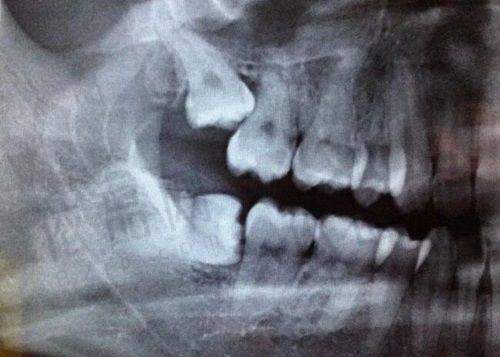

技术特色:医院拥有国有背景医生团队,擅长骨增量联合吸附修复,可解决牙槽骨吸收难题。还能开展双吸附技术,使吸附性义齿稳固性比传统方案提升1.8倍。

技术特色:做全口BPS吸附性义齿可采用闭口式印模技术,通过动态咬合记录减少食物嵌塞,尤其适合牙槽骨重度萎缩患者。而且,天津中幸口腔医院是天津河西区老牌机构,拥有10年以上吸附性义齿实例库,处理复杂实例经验充足。